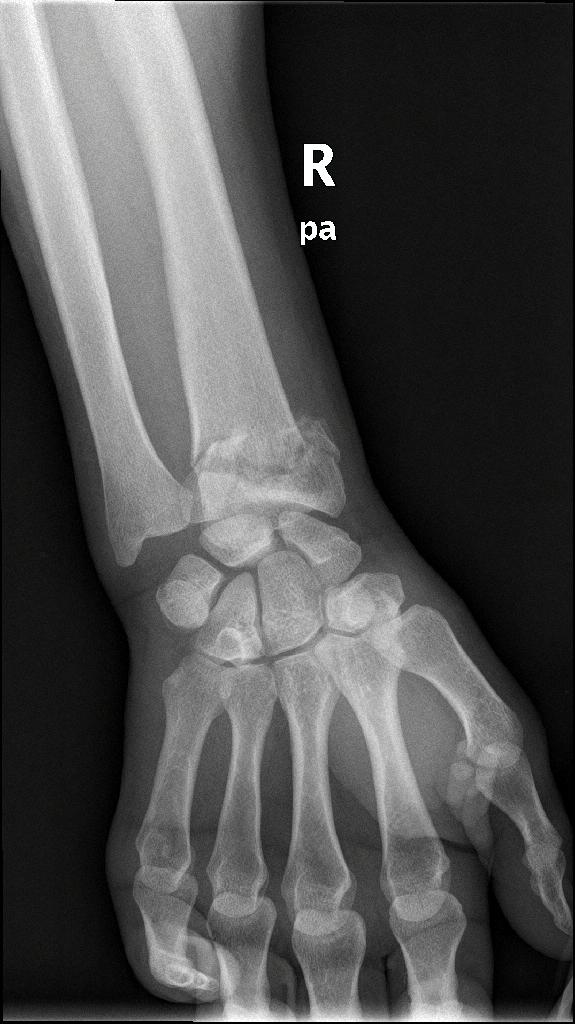

Κατάγματα κάτω πέρατος κερκίδος – κατάγματα Colle’s

Είναι τα συχνότερα κατάγματα στον σκελετό και συμβαίνουν συνήθως σε γυναίκες μετά την εμμηνόπαυση, όταν πέφτουν στο έδαφος και προσπαθούν με συγκρατηθούν βάζοντας την παλάμη. Τα πιο δύσκολα να αντιμετωπιστούν είναι εκείνα που επεκτείνονται μέχρι την αρθρική επιφάνεια.

Περίπτωση 1ου ασθενούς